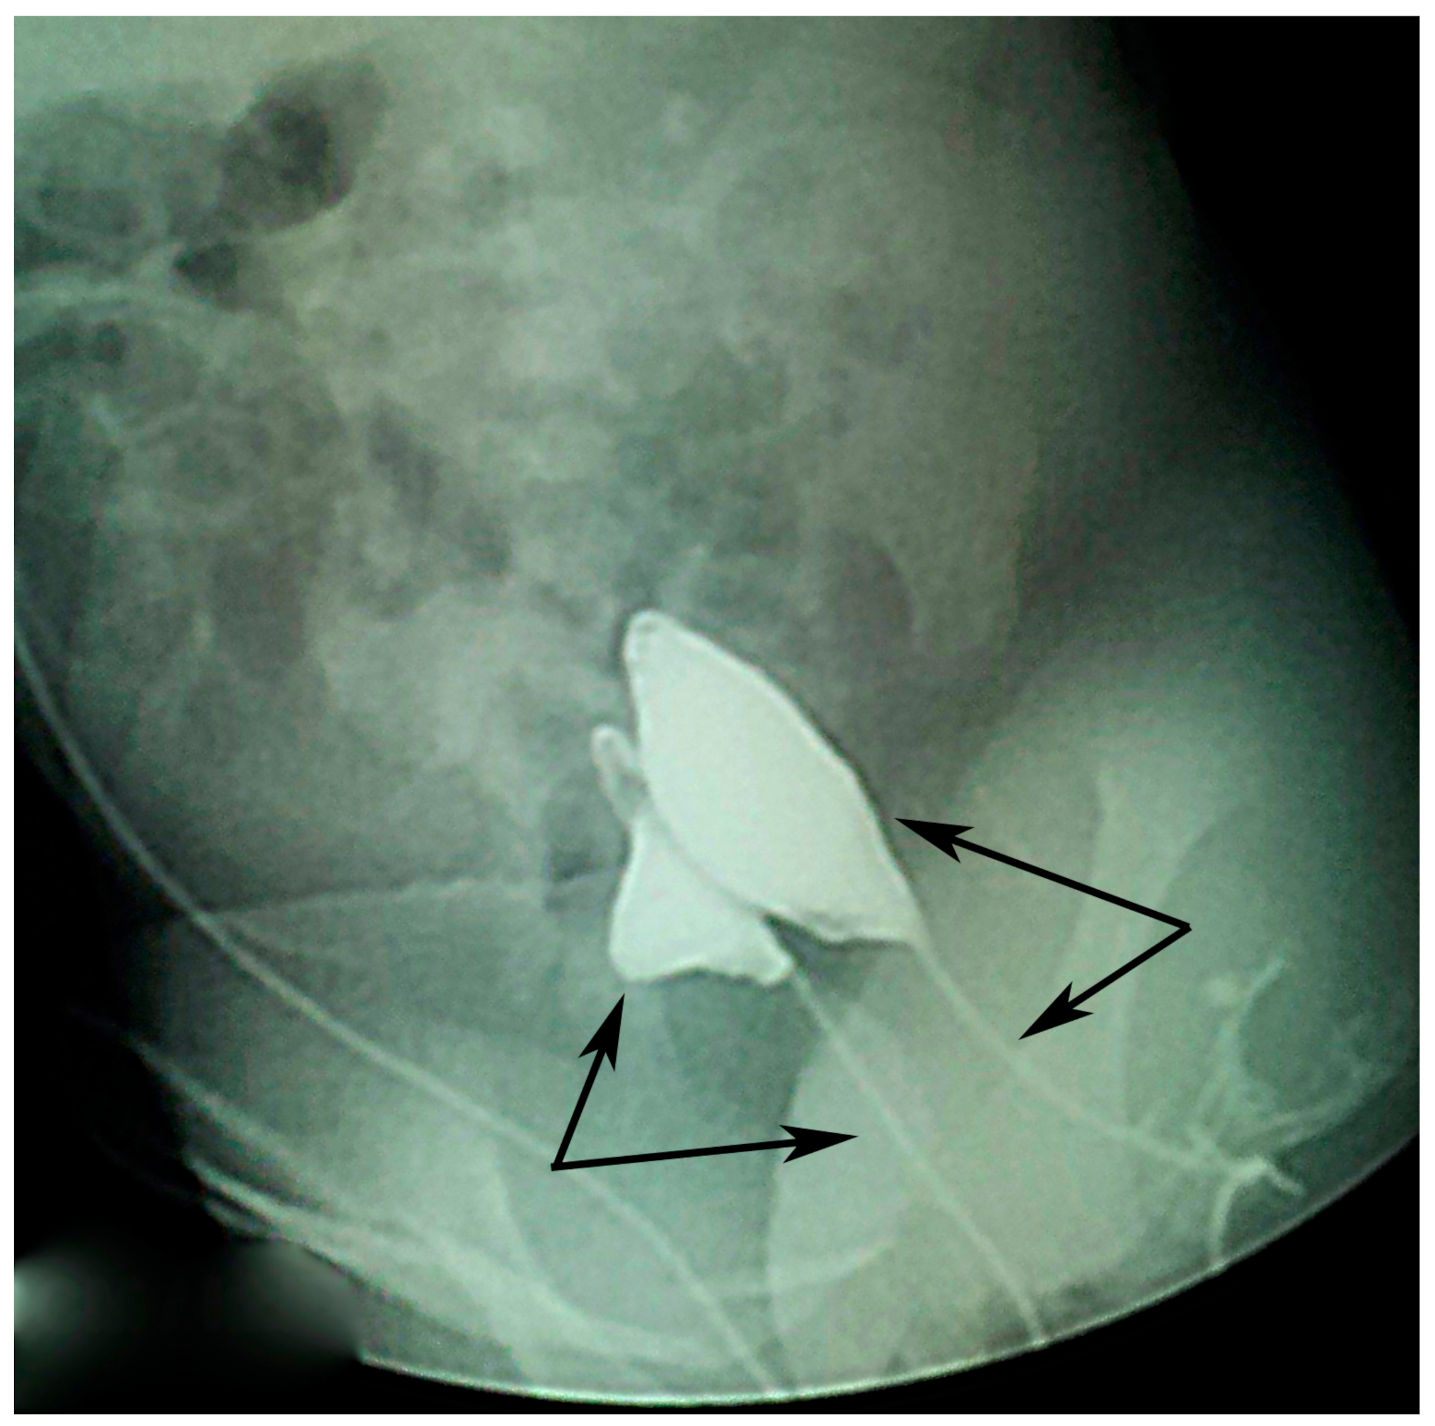

Voiding cystourethrogram done on both urethral openings (Figure 3) showed no signs of vesicoureteral reflux (VUR) but showed one smaller duplicated bladder and the duplicated urethras.

Figure 3. Voiding cystourethrogram shows no reflux, one smaller duplicated bladder, and duplicated urethra (arrows).